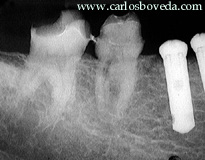

El paciente, de 46 años de edad, en aparente buen estado de salud general, nos es referido para evaluar endodónticamente el primer molar inferior derecho.

Estas opiniones de nuestros participantes reflejan sus criterios: Participante 1.- " É um dente com tecido pulpar com diminuição de volume fisiológica, tanto em razão do tempo de permanência do mesmo na cavidade bucal quanto das forças físicas que atuam no mesmo em razão de suportar uma coroa protética. Radiograficamente apresenta uma área radiolúcida na região do canal distal, sugerindo um processo de reabsorção interna. ". Participante 2.- " La evaluación clínica nos revela una evidente alteración del tejido pulpar, muy probablemente como resultado al tallado realizado en el molar. Sin observar la imagen radiográfica podríamos pensar inicialmente en una calcificación de ese tejido, sin embargo, radiográficamente esa alteración se evidencia como una resorción interna en la porción coronaria del conducto distal, y que aparentemente aún no ha involucrado el periodonto. ". Participante 3.- "creo que la raíz mesial , sus conductos se encuentran calcificados por lo que se observa radiograficamente. El conducto distal presenta una reabsorción interna a nivel de tercio cervicaly medio. ". Participante 4.- "Para mì es una pulpa stressada, al recibir el tallado para la corona. En las raìces mesiales, la pulpa reacciona calcificàndose, mientras que en raìz distal aparenta tener una reabsorciòn interna (digo aparenta, porque no puedo ver en la imàgen detalladamente, las caracterìsticas de dicha reabsorc.)Quizàs, el tallado ocasionò una hemmorragia pulpar, que termina en u na reabsorc. ". Participante 5.- "Por el estado clínico y radiográfico de la hemiarcada se puede deducir que este diente ha estado con una mala función por mucho tiempo, soportando todas las fuerzas antes de recibir los implantes en los premolares, por lo tanto ha sufrido cambios importantes en su anatomía radicular, en mi manera de ver, este diente esta sufriendo un proceso de anquilosis y calcificación de los conductos en la raíz mesial,en la raíz distal se puede observar una pequeña luz del conducto con una zona radiolúcida en el tercio cervical posiblemente sea una zona de reabsorción interna, no se puede definir claramente el ligamento periodontal y el tejido radicular se confunde con el tejido óseo, por obvias razones su respuesta a las pruebas de vitalidad están disminuídas ". Participante 6.- " Pareciese haber una resorcion en el tercio medio y coronal de la raiz distal ya sea interna o externa habria que verificar tomando rx mesioradial y distoradial para verififcar si la imagen se desplaza, la respuesta disminuida podria deberse a que alguno de los filetes todavia permanezca con vitalidad. ". Participante 7.- " este molar para mi tiene buen pronostico sin realizarle tratamiento de conductos, por lo que veo radiograficamente y la sintomatologia me hace pensar en una degeneracion calcica, y no veo la razon de realizarle tratamiento de conductos ". Participante 8.- " el molar radigraficamente no se observa conductos en la raiz mesial lo que nos indica una posible metamorfosis calcica, teniendo en cuenta la disminucion de respuesrta ante el estimulo termico. En las raices distales se observa una rarefacion en el tercio coronal del conducto, ". Participante 9.- " Desde el punto de vista radiográfico, este molar parece que tiene una calcificación de los conductos radiculares, la cual podría ser una razón de la dinminución en la capacidad de respuesta ante un estímulo químico o físico, ya que, la conducción nerviosa a travez de los conductos radiculares está disminuida. Por otra parte no se observa ninguna evidencia de afeccion apical ó periodontal. Otra prueba factible de la cacificación de los conductos es la edad del paciente, y la pieza estudiada. ". Participante 10.- "Pulpa sana. LO que llama la atencion es un agrandamiento de la entrada del conducto distal, que en realidad puede llegar a ser una bifurcación del cond. Distal ". Participante 11.- " Pulpa normal ". Participante 12.- " Molar inferior con dos raices , en la raíz distal se observa una zona radiolúcida en tercio cervical de aproximadamente de 1 cm de longitud, posiblememnte compatible con Reabsorción interna. Aparentemente los conductos mesiales se encuentran calcificados ( degeneración Pulpar Calcificante) ". Participante 13.- "aunque radiográficamente no se observa ensanchamiento del espacio del ligamento periodontal, ni ninguna imagen periapical, se observa disminución en el tamaño de la cámara pulpar y de los conducto radiculares por procesos de calcificación, lo que evidencia degeneración pulpar. ". Participante 14.- "Hay una clara retracción pulpar pero en cuanto alos conductos se refiere, parecen estar en una situación aparentemente normal. ". Participante 15.- " La situación pulpar de este molar, podría ser la de una rebsorción dentinaria interna (conducto distal), probablemente en los conducto mesiales tengamos una calcificación, todo esto por una alteración pulpar posiblemente causada por una mala refrigeración al tallado del muñon coronario. ". Participante 16.- "En los conductos mesiales y la cámara pulpar, existe una aparente calcificación parcial, mientras que en el conducto distal, se observa una aparente resorción interna; producto de un proceso inflamatorio crónico irreversible. De hecho responde a las pruebas térmicas, pero de forma disminuida debido a ese proceso crónico y a la aposición de dentina. Estamos en presencia de una pulpitis irreversible. ". Participante 17.- "Este molar aparentemente presenta una reacción pulpar inflamatoria, en donde el órgano pulpar reaccionó como medio de defensa con una resorción interna a nivel del conducto distal y una calcificación parcial de la pulpa a nivel de los conductos mesiales. ". Participante 18.- " Después de analizar los datos suministrados, este molar presenta un diagnóstico provisional de Pulpitis irreversible, ya que radiográfica y clínicamente hay evidencia de degeneración pulpar por la aparente calcificación de la cámara y de los conductos y por la imagen sugerente de resorción interna (sin embargo esto no se puede asegurar, se necesitarian radiografías con otras angulaciones). ". Participante 19.- "Debido a las imágenes radiográficas,las cuales sugieren la presencia de una resorción interna en el conducto distal y la presencia de calcificaciones y las respuestas obtenidas en las pruebas térmicas podemos diagnosticar la presencia de una pulpitis irreversible asintomática. ". Participante 20.- "De acuerdo a las imágenes radiográficas, a la sintomatología y a los resultados de las pruebas clínicas reportados, el molar observado presenta una pulpitis irreversible asintomática, por lo que se indicaría la realización de un tratamiento endodóntico previo a la confección de la restauración definitiva. ".

Nuestra actitud frente al caso : Coincidimos con la opinión de la mayoria de los participantes de este for, en el sentido que las evidencias muestran una pulpa patológica, particularmente por la resorción interna evidente en el conducto distal, por lo que se considera necesario ejecutar el tratamiento endodónticoÑ